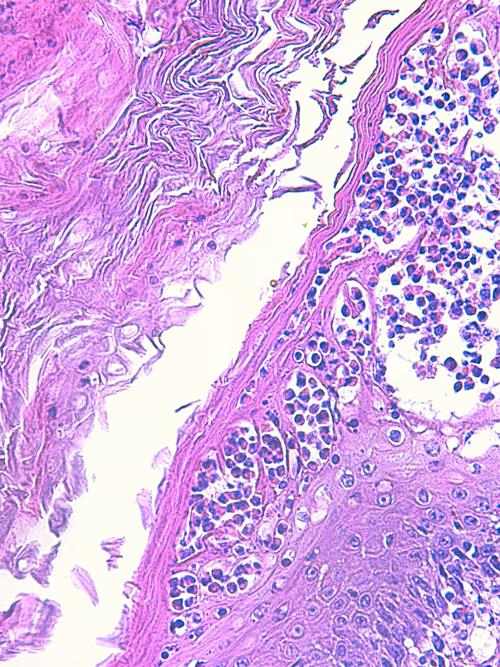

Photo 1 (Hémalun Eosine X 40) peau velue: L’épiderme et les infundibula folliculaires

sont hyperplasiques et hyperkératosiques. Les infundibula folliculaires sont le siège de pustules luminales et

pariétales, avec des fissurations linéaires parallèles au grand axe des follicules.

Le derme montre un inflammation péri-vasculaire et folliculo-centrée à diffuse.

Légendes de la Photo 1 :

- Double flèche bleue pointillée : grand axe des infundibula folliculaires à gaine épithéliale hyperplasique

- Double flèche verte : derme

- Ovales jaunes : pustules dans la paroi des follicules pileux

- Flèches jaunes : fissures linéaires dans la paroi des follicules pileux qui sont parallèles au grand axe des infundibula folliculaires

- Étoiles vertes évidées : lumière d’un follicule pileux hyperkératosique occupée par de la kératine et couche cornée hyperkératosique

- Étoiles rouges pleines : infiltrat dermique périvasculaire, périannexiel à diffus

- Étoiles turquoises pleines : lumière de follicules pileux obstruée de débris inflammatoires